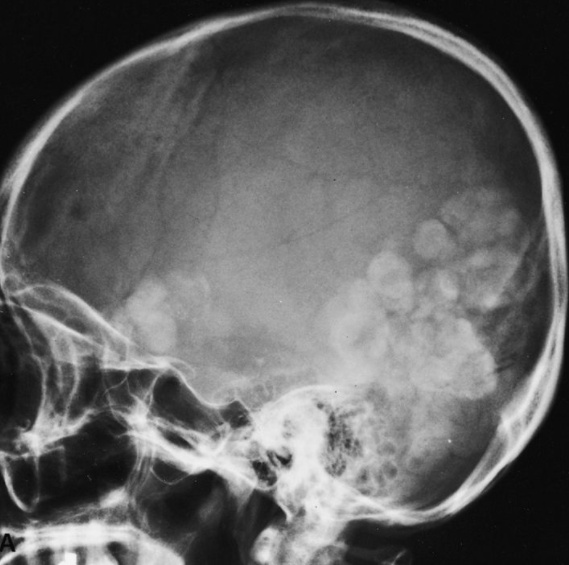

farmer on left. Cactus: fungus balls. Aspergillomas form in cavities, such as in TB/klebsiella cavities. People with cavities in lungs already are at risk

peanuts underground: Aspergillomas are gravity-dependent, fungus at bottom of cavity on chest xray